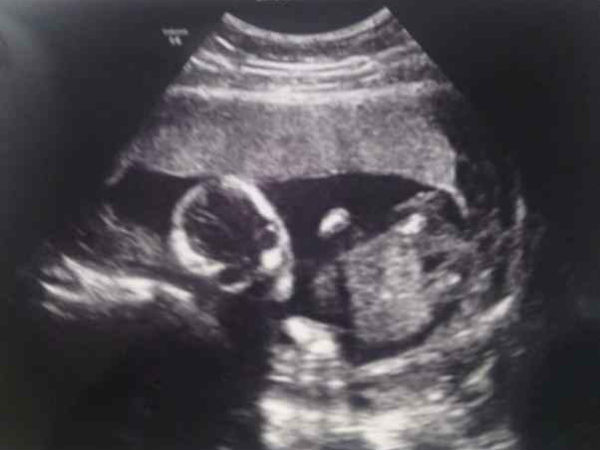

ಚಿತ್ರ#2 ಈ ಮಗು ನಿಮ್ಮನ್ನೇ ದುರುಗುಟ್ಟುತ್ತಿದೆಯೇ?

ಕೆಲವರಿಗೆ ಚಿತ್ರ ತೆಗೆಯುವಾಗ ಕ್ಯಾಮೆರಾ ಕಡೆ ದುರುಗುಟ್ಟಿ ನೋಡುವ ಅಭ್ಯಾಸವಿರುತ್ತದೆ. ಈ ಮಗು ಈ ಕಲೆಯನ್ನು ಹುಟ್ಟುವುದಕ್ಕಿಂತಲೂ ಮೊದಲೇ ಕಲಿತುಕೊಂಡಿದೆಯೇ ಎಂದು ಈ ಚಿತ್ರವನ್ನು ನೋಡಿದಾಗ ಅನ್ನಿಸುತ್ತದೆ. ಅದರಲ್ಲೂ ಮಗುವಿನ ಕಣ್ಣುಗಳು ನಿಮ್ಮನ್ನೇ ದಿಟ್ಟಿಸಿ ನೋಡುತ್ತಿರುವಂತೆ ಕಾಣಿಸುತ್ತದೆ. ಈ ಚಿತ್ರವನ್ನು ಅಂದು ನೇರವಾಗಿ ನೋಡಿದವರಿಗೆ ಒಂದೆರಡು ದಿನವಾದರೂ ಈ ಮಗುವಿನ ಕಣ್ಣುಗಳು ಖಂಡಿತಾ ಕಾಡಿರಬಹುದು.